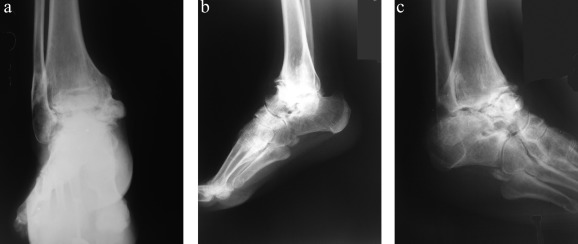

A short leg non-weight-bearing cast was applied postoperatively for 8–12 weeks. After cast removal, gradual weight-bearing was allowed with solid ankle foot orthoses until solid healing was observed. Full weight-bearing was permitted when solid fusion was achieved according to clinical and radiological examination. At 6 weeks, 3 months, 6 months, and 1 year postoperatively, X-rays were obtained to evaluate ankle fusion (Fig. 1  ;  Fig. 2 a, b).

(a–c). Preoperative anteroposterior-lateral and oblique X-ray views of ...

Fig. 1.

(a–c). Preoperative anteroposterior-lateral and oblique X-ray views of 56-year-old female ankle arthrosis patient.